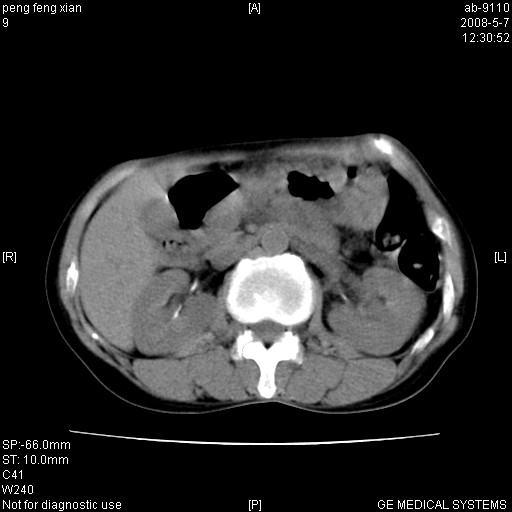

女,56岁。b超左一腹包块,考虑胃肠道肿瘤。

胃底占位待出;右肾结石?

胃体部胃壁增厚,不均匀性强化,与胰腺分解欠情.

考虑:胃癌,胰腺受侵待除外.

典型胃癌胰体尾部受侵。